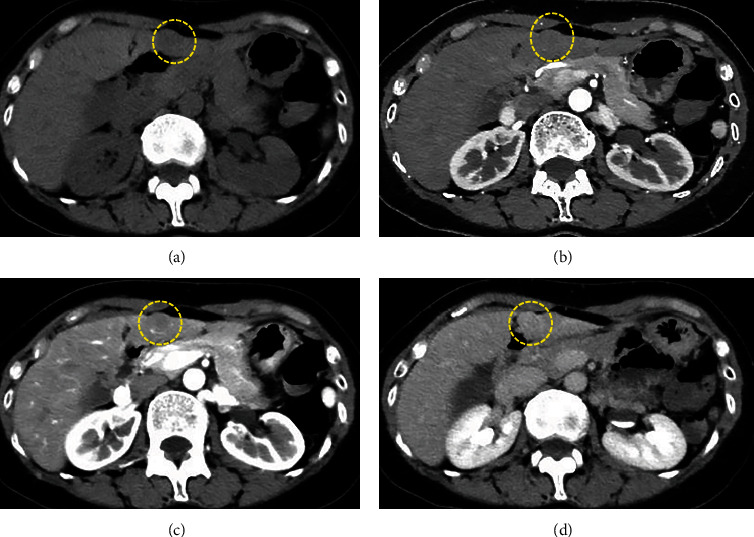

反应性淋巴细胞增生(RLH)是一种良性疾病,很少发生在肝脏。有报告称,反应性免疫现象与该病的发生有关,但真正的发病机制尚不清楚。目前还没有与炎症性肠病相关的病例报道。我们报告了一例溃疡性结肠炎(UC)患者的肝脏 RLH 病例。一名 55 岁的 UC 女性患者因腹痛前往门诊就诊,医生诊断为急性阑尾炎,并开了抗生素。影像学检查发现肝脏有肿块,但排除了阑尾炎的可能。疼痛好转后,她被转到我院接受进一步检查。超声波检查发现肝脏内有一个 12 毫米的低回声肿块。计算机断层扫描和磁共振成像没有发现典型的恶性病变。医生建议定期进行影像随访,但患者强烈要求手术治疗,因为他有家族恶性疾病史。患者接受了腹腔镜肝部分切除术。组织病理学检查结果显示,淋巴滤泡呈聚集性增生,并伴有生发中心。浸润的淋巴细胞未见新生物。最终诊断为肝脏 RLH。UC 是一种慢性炎症性肠病,可能与 RLH 有关,但目前尚无明确的解释。这是已知的首例 UC 患者肝脏 RLH 病例。但 RLH 与 UC 之间的关系仍不确定。有必要进行进一步的调查和病例积累。

Reactive lymphoid hyperplasia (RLH) is a benign disease, rarely occurring in the liver. Reactive immune phenomenon has been reported in association with its occurrence, but the true pathogenesis is unknown. No case was reported in association with inflammatory bowel disease. We report a case of RLH of the liver in a patient with ulcerative colitis (UC). A 55-year-old woman with UC went to the outpatient clinic with abdominal pain, and antibiotics were prescribed with diagnosis of acute appendicitis. Imaging study detected a mass in the liver but ruled out appendicitis. She was referred to our hospital for further examination after pain improving. A 12 mm hypoechoic mass was detected in the liver on ultrasonography. There were no typical malignant findings on computed tomography and magnetic resonance imaging. Regular image follow-up was recommended, but the patient strongly requested surgery because of family history of malignant disease. Laparoscopic partial hepatectomy was performed. Histopathological findings revealed a conglomerate hyperplasia of lymphoid follicles with germinal centers. Infiltrating lymphocytes were non-neoplastic. Final diagnosis was RLH of the liver. UC is chronic inflammatory bowel disease and may be related to RLH, but there is no clear explanation at this point. This is the first known reported case of RLH of the liver in a patient with UC. But the relationship between the RLH and UC remains uncertain. Further investigation and case accumulation are necessary.